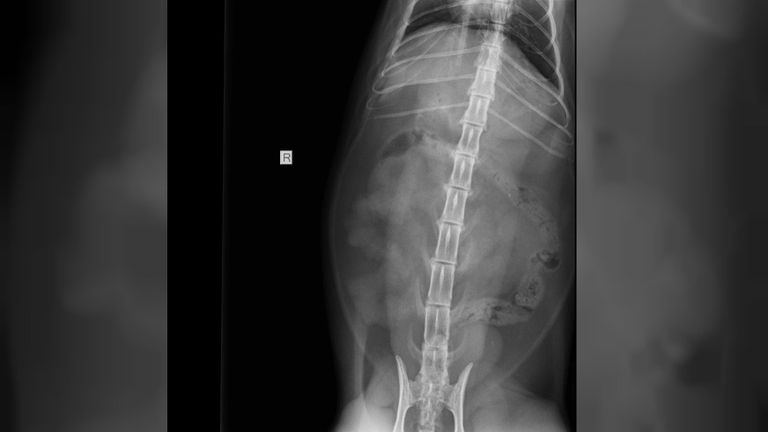

"We maakten röntgenfoto's en daarop was te zien dat zijn darm helemaal opgestroopt was om de slinger." Een levensgevaarlijke situatie, volgens Rimi. "Als je aan het draadje trekt, beschadig je de darm aan de binnenkant. Opereren was de enige optie om grote wonden te voorkomen. Anders was Rudy nu dood geweest. Ik heb de darm op vier plekken opengesneden om de slinger eruit te krijgen."

Zo zat de slinger in Rudy's darmen: